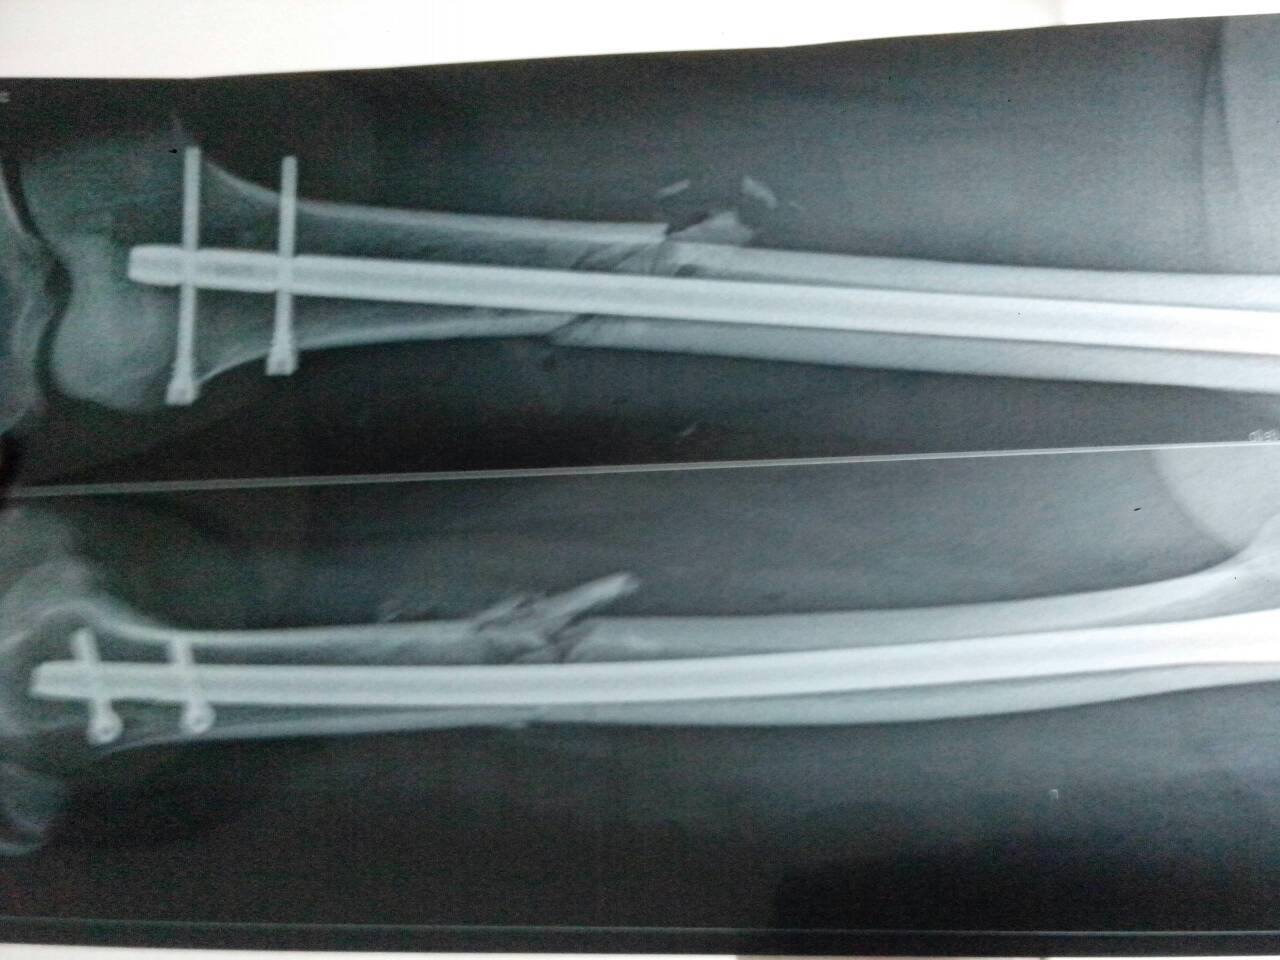

我是车祸导致左大腿骨干骨折,做手术至今有八个月了,为什么走路还是一拐一拐的,膝关节疼痛。当时做的是内髓钉固定术。求解!

病情分析: 你好,看了你上传图片,感觉你的手术做的很好。 指导意见: 但是要想痊愈估计至少需要二年时间,所以建议你不要急躁,如果有疼痛可以对患处进行适当热敷。